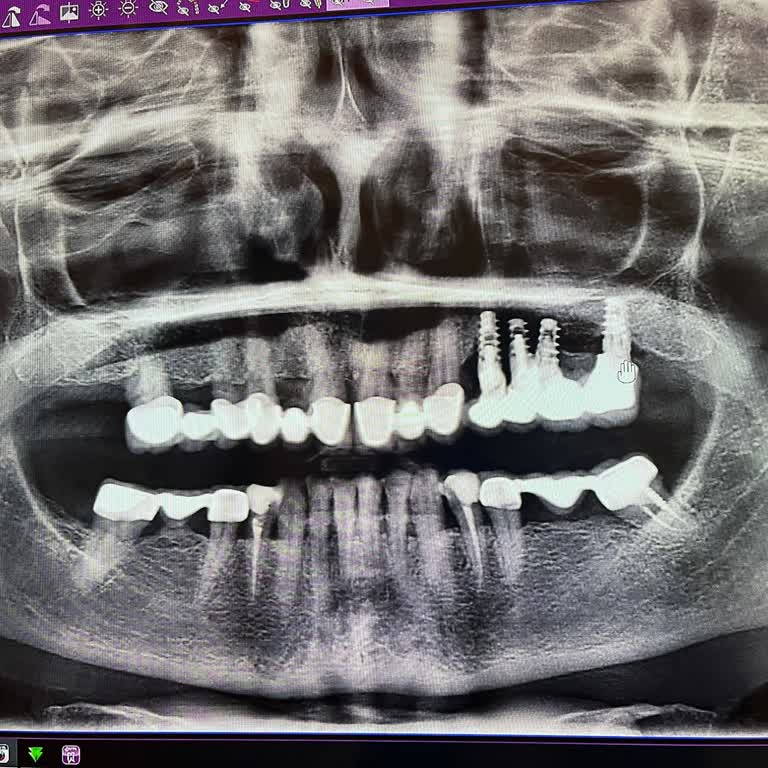

Estetica Dental Gümbet şubesinde, yaklaşık 7 yıl sorunsuz kullandığım kaplamalarımda yaşadığım şiddetli diş ağrısı nedeniyle 2024 Eylül ayında tekrar tedaviye başladım. Eski kaplamalarım söküldü, ön dişlerimde temizlik işlemi yapıldı ve bu işlemden sonra dişlerimde sallanmalar ortaya çıktı. Bunun üzerine alt çenemdeki tüm dişlerin yapılmasına karar verildi, iki implant uygulandı ve kalan dişlerime zirkonyum kaplamalar yapıldı.

Tedavi sürecinde kanal tedavisi eksik olan tek bir dişim olduğunu, bunun neden yapılmadığını defalarca sormama rağmen bu dişin sağlam olduğu ve "öldürmeye gerek olmadığı" söylendi. Tedavi tamamlanıp kaplamalar takıldıktan kısa süre sonra, kanal tedavisi yapılmayan bu dişimin dibinde şişmeler ve enfeksiyon oluştu. Ayrıca zirkonyum kaplama yapılan iki dişimde kaplamalar yerinden çıktı. Tekrar taktırmaya gittiğimde ise diş etimin çekildiği, bu dişlerin kökten sallanmaya başladığı ve çekilip implant yapılması gerektiği söylendi.

Tüm bu süreçte Söke’den Gümbet şubesine defalarca gidip gelmek zorunda kaldım, hem ciddi zaman hem de yüksek miktarda para harcadım. Buna rağmen tedaviden beklediğim sonucu alamadığım gibi, dişlerimle ilgili yeni problemler ve ağrılar yaşamaya başladım. Kanal tedavisi yapılmayan dişimin enfeksiyon ve şişlik yapması, kaplamaların kısa sürede düşmesi ve dişlerimin kökten sallanacak duruma gelmesi nedeniyle sürecin doğru planlanmadığını ve mağdur edildiğimi düşünüyorum.